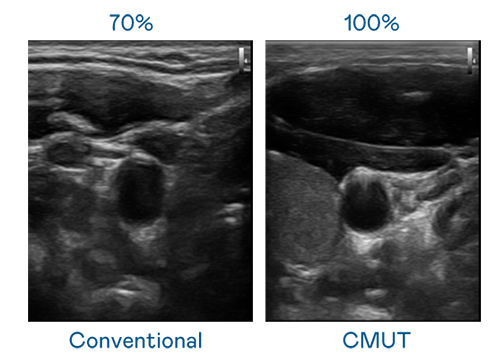

CMUT 技术是一种用电容式微机电元件来产生超音波讯号的技术。与传统 PZT 压电式技术相比,CMUT 频宽增加 30%,更宽频的超音波讯号让影像解析度大幅提升,是实现高影像品质医疗超音波扫描、促进精准医疗发展的关键技术。

大频宽带来超清晰影像

超音波影像的解析度高低,首先取决于探头能发出的讯号频宽。asiagame CMUT 可提供高清晰的超音波讯号,提供高频宽、高灵敏度、影像纹理细节更高的超音波影像,协助医护人员缩短影像判读时间及利用精准的医疗影像进行诊断。